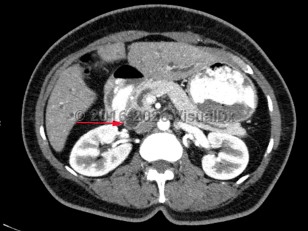

Imaging Studies image of Carcinoma of the ampulla of Vater - imageId=8367516. Click to open in gallery.  caption: '<span>Contrast enhanced CT scan of abdomen and pelvis demonstrates ampullary carcinoma with duct dilatation.</span>'

Contrast enhanced CT scan of abdomen and pelvis demonstrates ampullary carcinoma with duct dilatation.